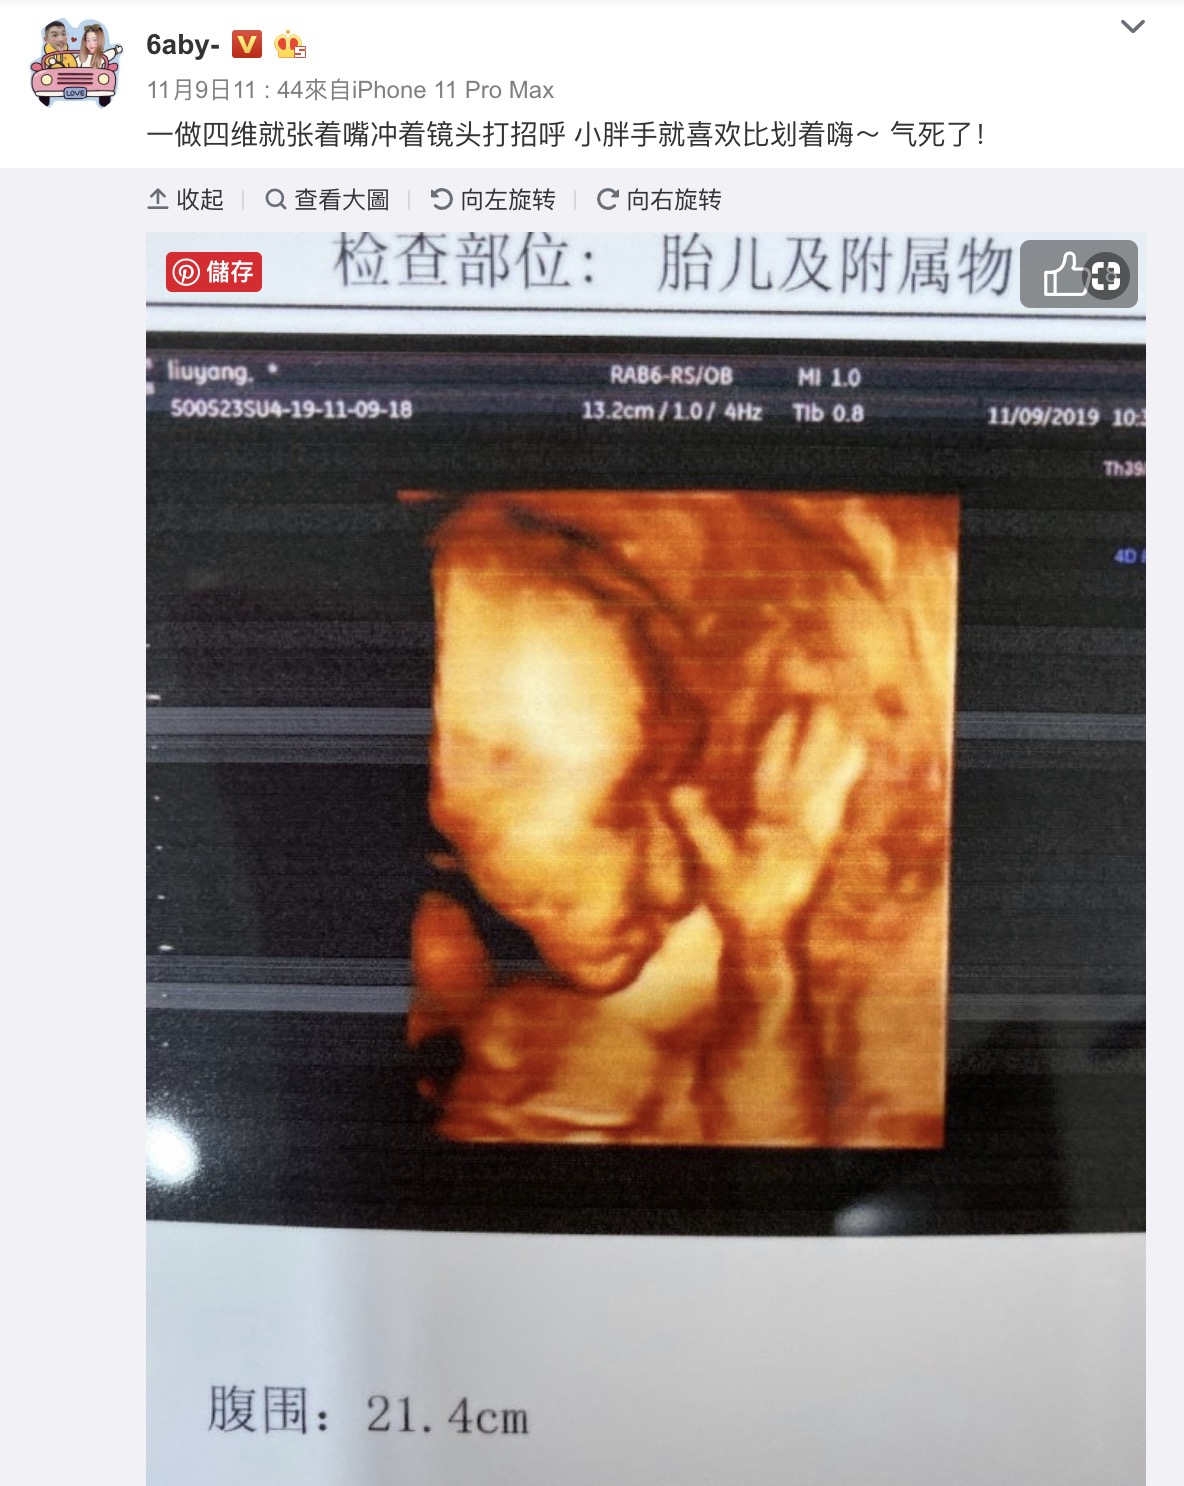

小可愛在懷孕後也時常會在微博上發文與網友們分享各種酸甜苦辣,她曾曬出一張小孩的超音波照,畫面中小孩伸出了手放在鼻子前面,做了一個神似打招呼的姿勢,小可愛也發文寫下:「一做四維就張著嘴衝著鏡頭打招呼 小胖手就喜歡比劃著嗨~ 氣死了!」,更在一旁附上羊羊羊學小孩動作的照片,看上去兩人的相似度非常高。而在懷孕32周時,小可愛曬出兩張對著鏡子的自拍照,畫面中她的孕肚已經是頭的兩倍大,許多網友更發現她的孕肚上絲毫沒有妊娠紋,羨慕的說道:「沒有妊娠紋是怎麼做到的呀!」、「你肚肚上居然沒有紋欸」。